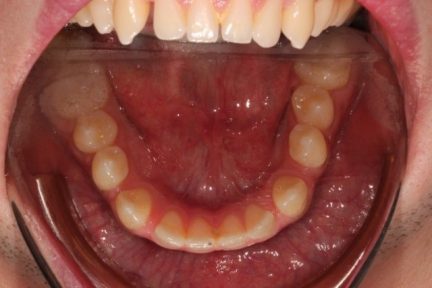

- Nous avons commencé par élargir l'arcade supérieure et perdre du couple sur les incisives inférieures

- Après 19 aligners, nous avons effectué une réduction interproximale sur l'arcade inférieure et utilisé l'effet de chaîne en C pour fermer tous les espaces

État final